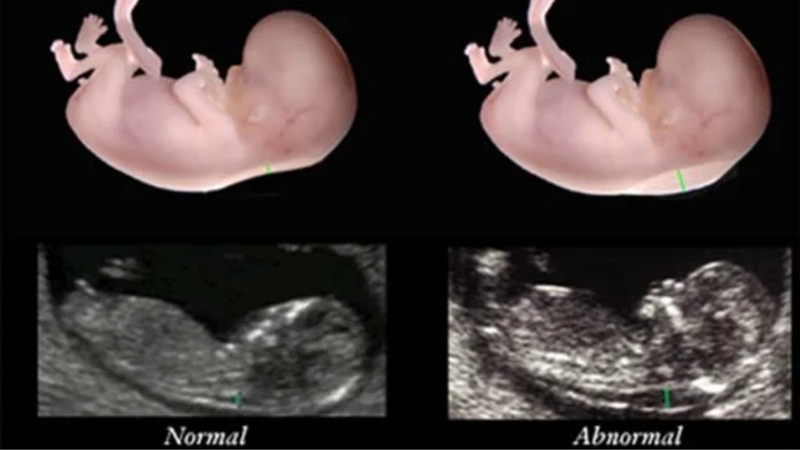

Các chuyên gia đã nghiên cứu và xác định các thông số chuẩn để đánh giá khả năng mắc hội chứng Down và các bất thường nhiễm sắc thể khác ở thai nhi. Do đó, thai nhi có kích thước đầu và xương chậu từ 45 - 84 mm thường có độ mờ da gáy dưới 2,5 mm. Trẻ có độ mờ da gáy dưới 1,3 mm có nguy cơ mắc hội chứng Down tương đối thấp. Trên hình ảnh siêu âm, độ mờ da gáy là khoảng cách giữa hai điểm được bác sĩ đánh dấu.

Trên hình ảnh siêu âm, độ mờ da gáy là khoảng cách giữa hai điểm được bác sĩ đánh dấu